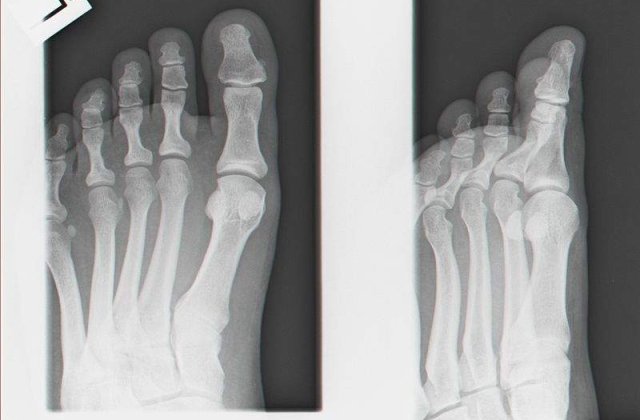

"Piciorul de om" era de fapt o laba de urs congelata, scrie jurnalul.ro.

Descoperirea macabra a fost facuta dupa ce bagajul a fost scanat. Angajatii l-au deschis si au gasit un picior de om, sectionat de la glezna.